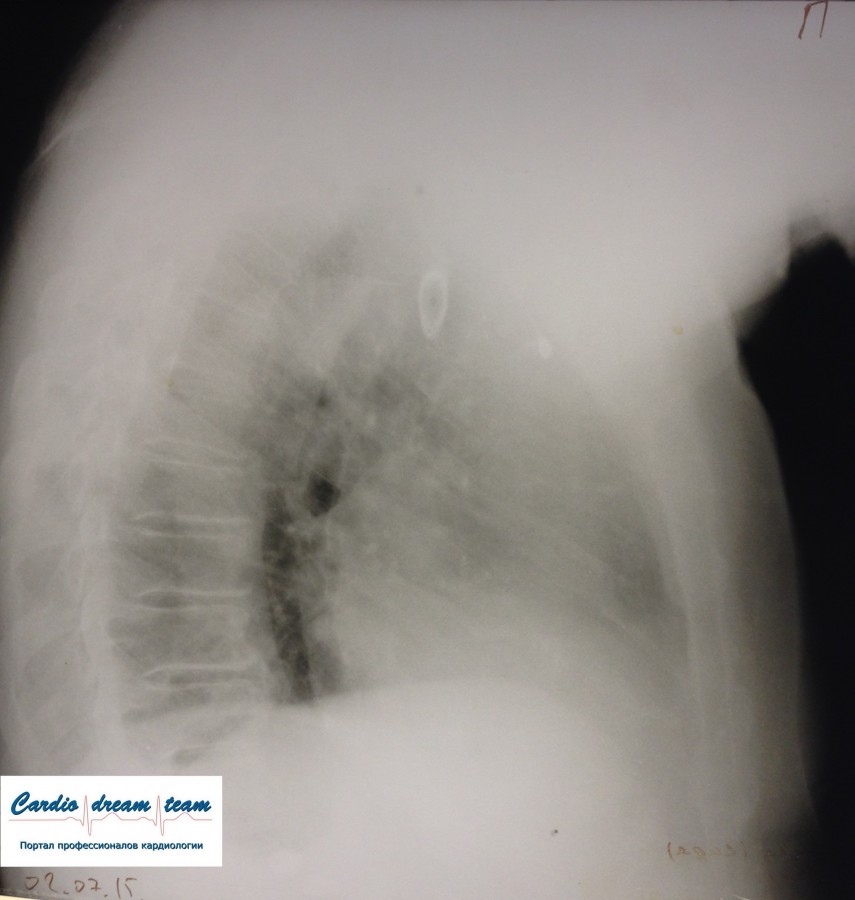

Осумкованный плеврит

Обсуждалось здесь https://vk.com/club84409679?w=wall-84409679_8836%2Fall

IMG_4626%C2%A0— копия.jpg

IMG_4626%C2%A0— копия.jpg [ 186.57 KiB | Просмотров: 16402 ]